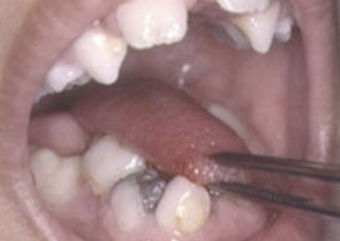

abnormally short, thick lingual frenum resulting in limitation of tongue movement

ankyloglossia

tx for ankyloglossia

frenectomy